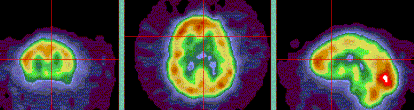

Three brain scans with color gradients indicating different levels of activity.

Information from these studies allow our specialists to detect, diagnose and monitor diseases and conditions ranging from cancer to Alzheimer’s disease. Your care team will then work with you to determine the best treatment strategy.